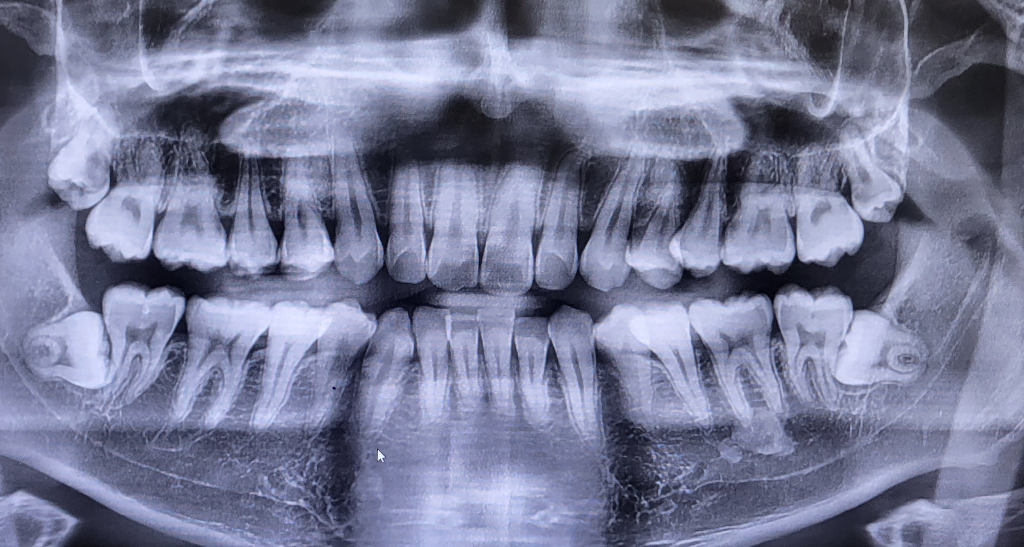

위에 사랑니때문에 병원을 갔는데 아래사랑니가 발견돼서 발치반드시해야 나중에 40대50대돼서도 치아건강유지할 수 있겠죠?.. 현재 연나이 25세인데 무섭네요.. 아래 사랑니 저정도면 발치난이도가 높은편인가요?

완전매복사랑니이고 옆 어금니와 위치관계상 다소 어려운 발치가 될 것 같습니다. 또한 아래턱 신경과도 거리가 매우 가까우므로 CT등을 추가적으로 촬영해 사랑니와 신경관 사이의 정확한 위치 관계를 파악하고 안전하게 뽑는 것이 좋을 것 같습니다.

상악의 사랑니는 크게 어려운건 아니지만, 하악의 사랑니는 사랑니를 전문적으로 뽑으시는 선생님께 발치를 하시는게 좋을것같습니다.

현재 사진상에 매복사랑니 보이며, 매복 사랑니를 그냥 두면 바로 앞 어금니를 상하게 하는 가능한 빨리 뽑는 것이 좋습니다. 지금 당장

통증 없다고 두면 바로 앞 어금니가 서서히 상하게 되어 앞의 어금니와 함께 뽑아야 할수 있습니다.

발치난이도가 높은 편이기에 매복 사랑니 발치 경험이 풍부한 구강외과전문의에게 치료를 받길 권합니다.